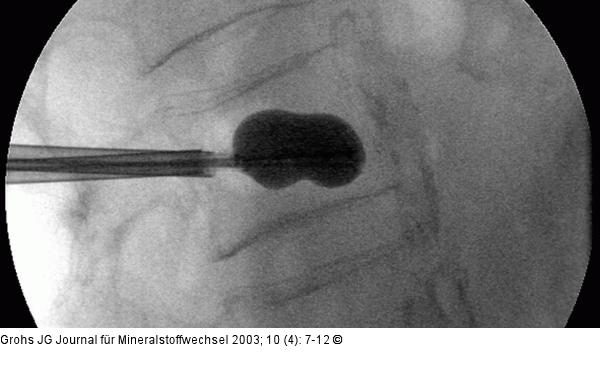

Abbildung 4: Ballon-Kyphoplastik Aufblähen des Ballons im Wirbelkörper unter Durchleuchtung und Kontrolle von Druck und Volumen. |

Aufblähen des Ballons im Wirbelkörper unter Durchleuchtung und Kontrolle von Druck und Volumen. |